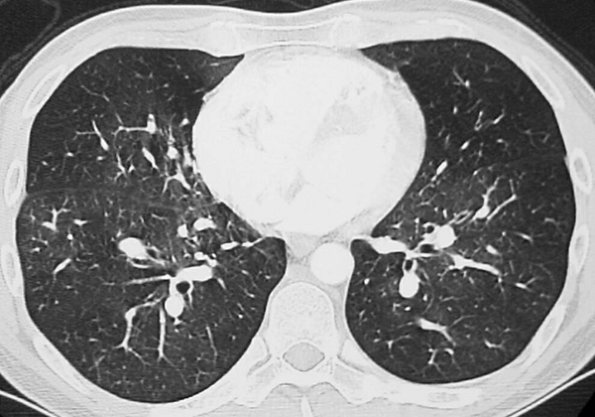

Tumors most commonly known to embolize through the pulmonary arterial circulation include bronchioloalveolar carcinoma; carcinomas of the breast, kidney, stomach, liver, and prostate; and choriocarcinoma (16). The characteristic CT features are dilatation and beading of peripheral pulmonary arteries

P.286

(Fig. 17-29). The appearance can resemble the "tree-in-bud" appearance of small airway disease (17). Maximum-intensity-projection images can be helpful in showing continuity of the distal vessels with more central pulmonary vessels in cases of tumor emboli. Many more cases of tumor emboli are discovered at autopsy than antemortem.

FIGURE 17-29. Tumor emboli. A: CT of a 16-year-old boy with a large pelvic sarcoma shows dilated and beaded peripheral pulmonary arteries (arrows). B: Maximum-intensity-projection image shows the continuity of these abnormal vessels with the central pulmonary arteries.